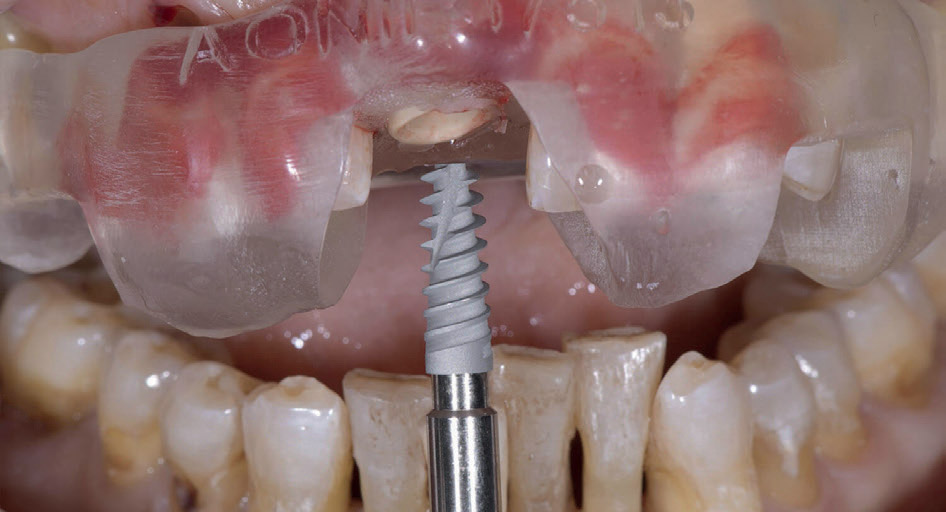

In seguito ad estrazione atraumatica si posiziona impianto AON REVCON IS-Four mediante chirurgia guidata (fig.2).

Fig. 2

In seguito ad estrazione atraumatica si posiziona impianto AON REVCON IS-Four mediante chirurgia guidata (fig.2).

Fig. 2